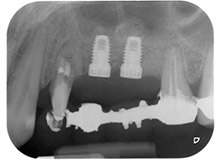

Fig. 1: Paziente di 58 anni. La radiografia preoperatoria mostra una lesione periodontale apicale in corrispondenza del dente 24 e una perdita orizzontale di tessuto osseo alveolare nel secondo quadrante.

Una paziente donna di 58 anni lamentava dolore e aumentata mobilità del dente di appoggio del ponte 24. Era presente infiammazione periodontale con tasche di profondità di 7 mm a livello mesiobuccale e di più di 12 mm a livello distale, nonché coinvolgimento di terzo grado della forcazione. Inoltre, la radiografia rivelava una lesione periodontale estensiva attorno alla regione apicale del dente pretrattato 24 (in altro luogo) a livello endodontico (Fig. 1).

Un anno più tardi, sono stati estratti i denti 25 e 26 in seguito a trauma e per motivi endoperiodontali, prima del posizionamento del ponte. Era stata diagnosticata una lesione endoperiodontale combinata in corrispondenza del dente 24, di eziologia incerta. La paziente desiderava conservare i denti 24 e 27 di appoggio al ponte e non accettava una protesi rimovibile finale, o temporanea. Si è pertanto deciso di fare il possibile per conservare entrambi i denti, nonostante la prognosi negativa basata sugli esiti clinici e radiologici.